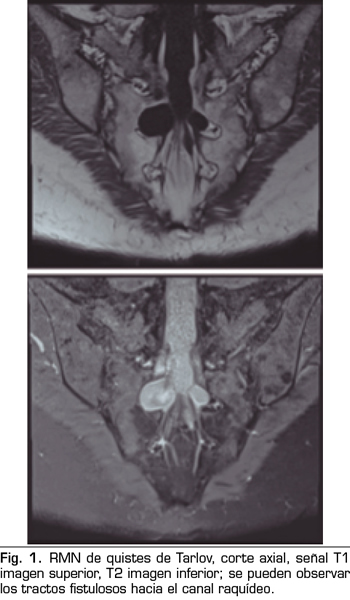

Los “quistes perineurales” o “Quistes de Tarlov” son alteraciones en la duramadre de las raíces nerviosas, que se producen más frecuentemente en la zona sacra. El diagnóstico suele ser casual mediante RMN; la incidencia es variable, debido a que el hallazgo es incidental. Habitualmente son asintomáticos, pero pueden producir radiculopatía, dolor perineal o vejiga neurógena, entre otros.

The diagnosis is usually casual by magnetic resonance. The incidence is variable, because the finding is incidental. The are usually asymptotic, but can cause radiculopathy, perineural pain or neurogenic bladder.

Figura 2